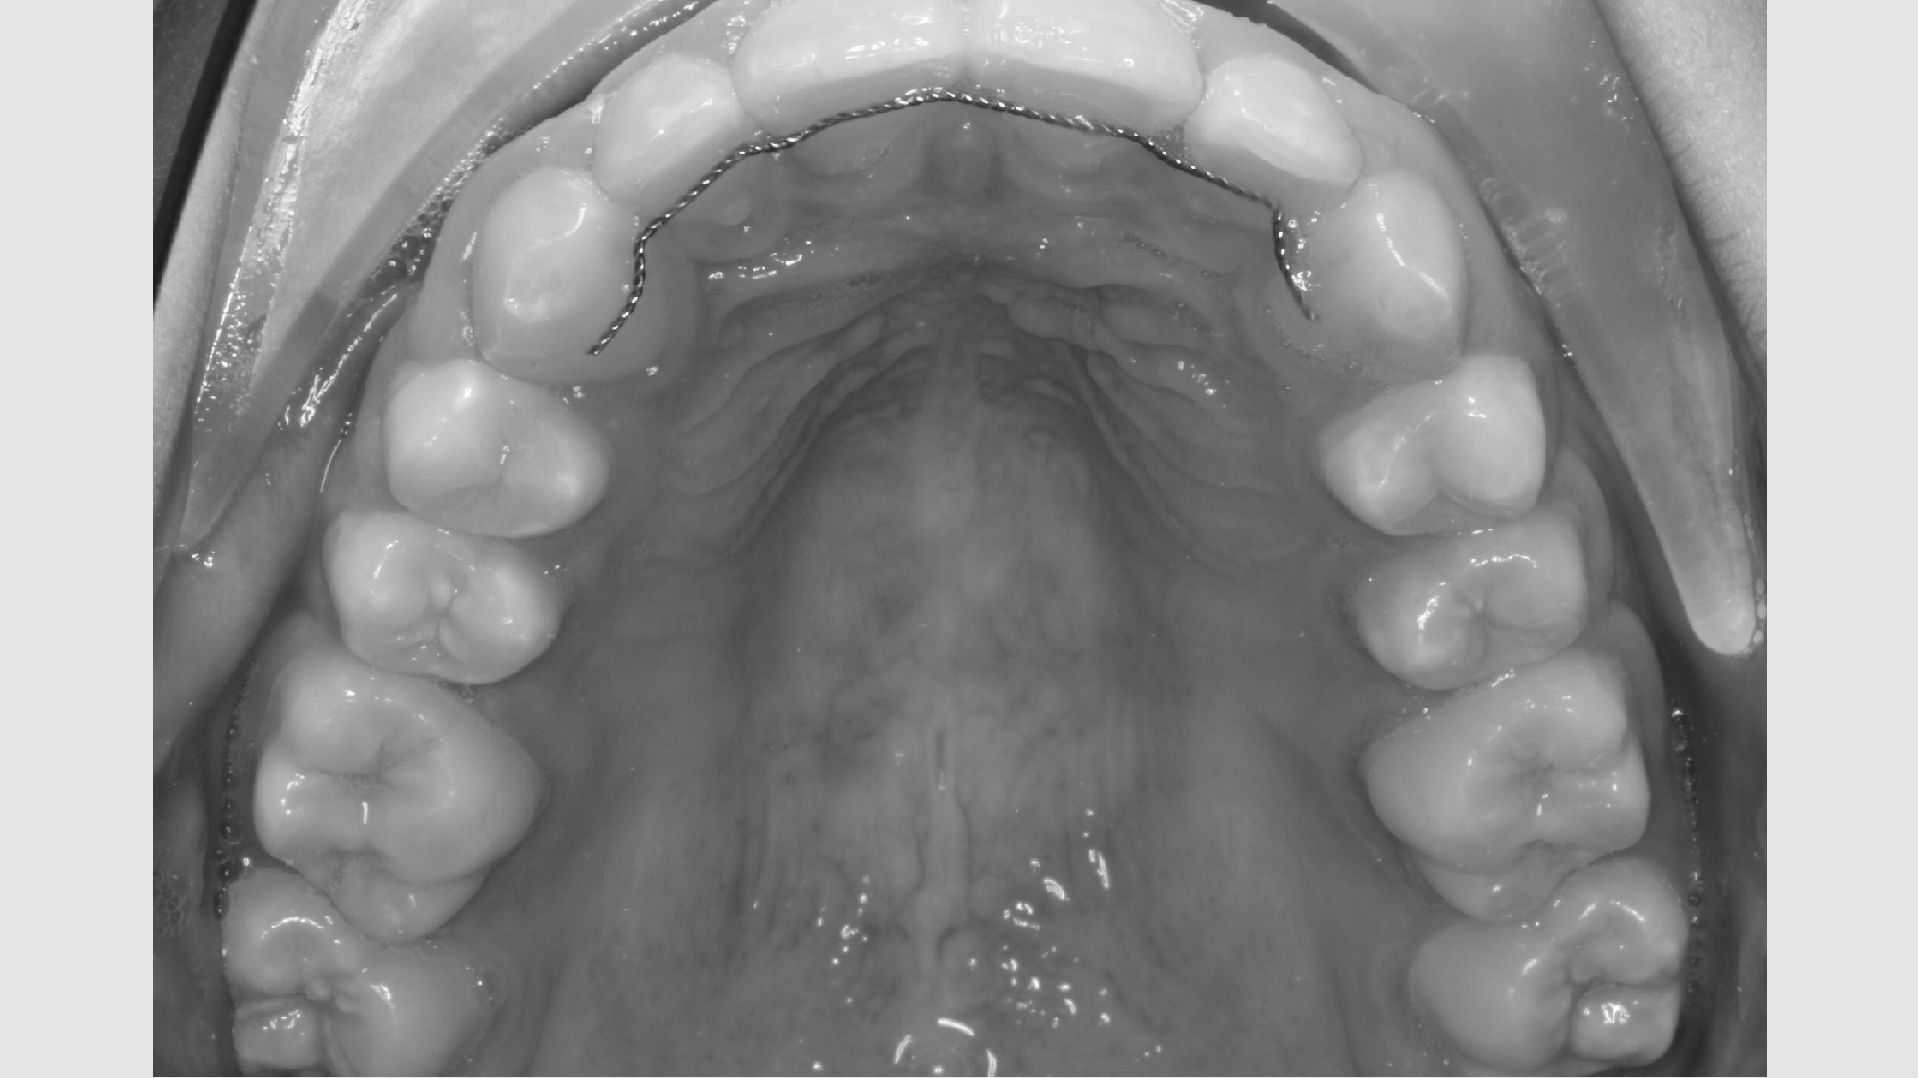

Første gang dit barn besøger Tandreguleringsklinikken, bliver der lavet studiemateriale.

Studiemateriale, består af modeller, fotos og røntgenbilleder af tænder og ansigt. Der bliver også udleveret et helbredsskema, som skal udfyldes på stedet. Det er vigtigt at vide, om jeres barn er sundt og raskt, eller om der er særlige hensyn, vi skal tage - eksempelvis til medicin med videre.

Der bliver taget billeder "udenpå og indeni" samt røntgenbilleder.

Dit barn skal selv holde sine læber til side med en læbeholder, mens tænderne bliver fotograferet. Billederne har følgende formål:

- Panorama viser, om alle tænder er anlagt, og om tandrødder og kæbeled ser normale ud.